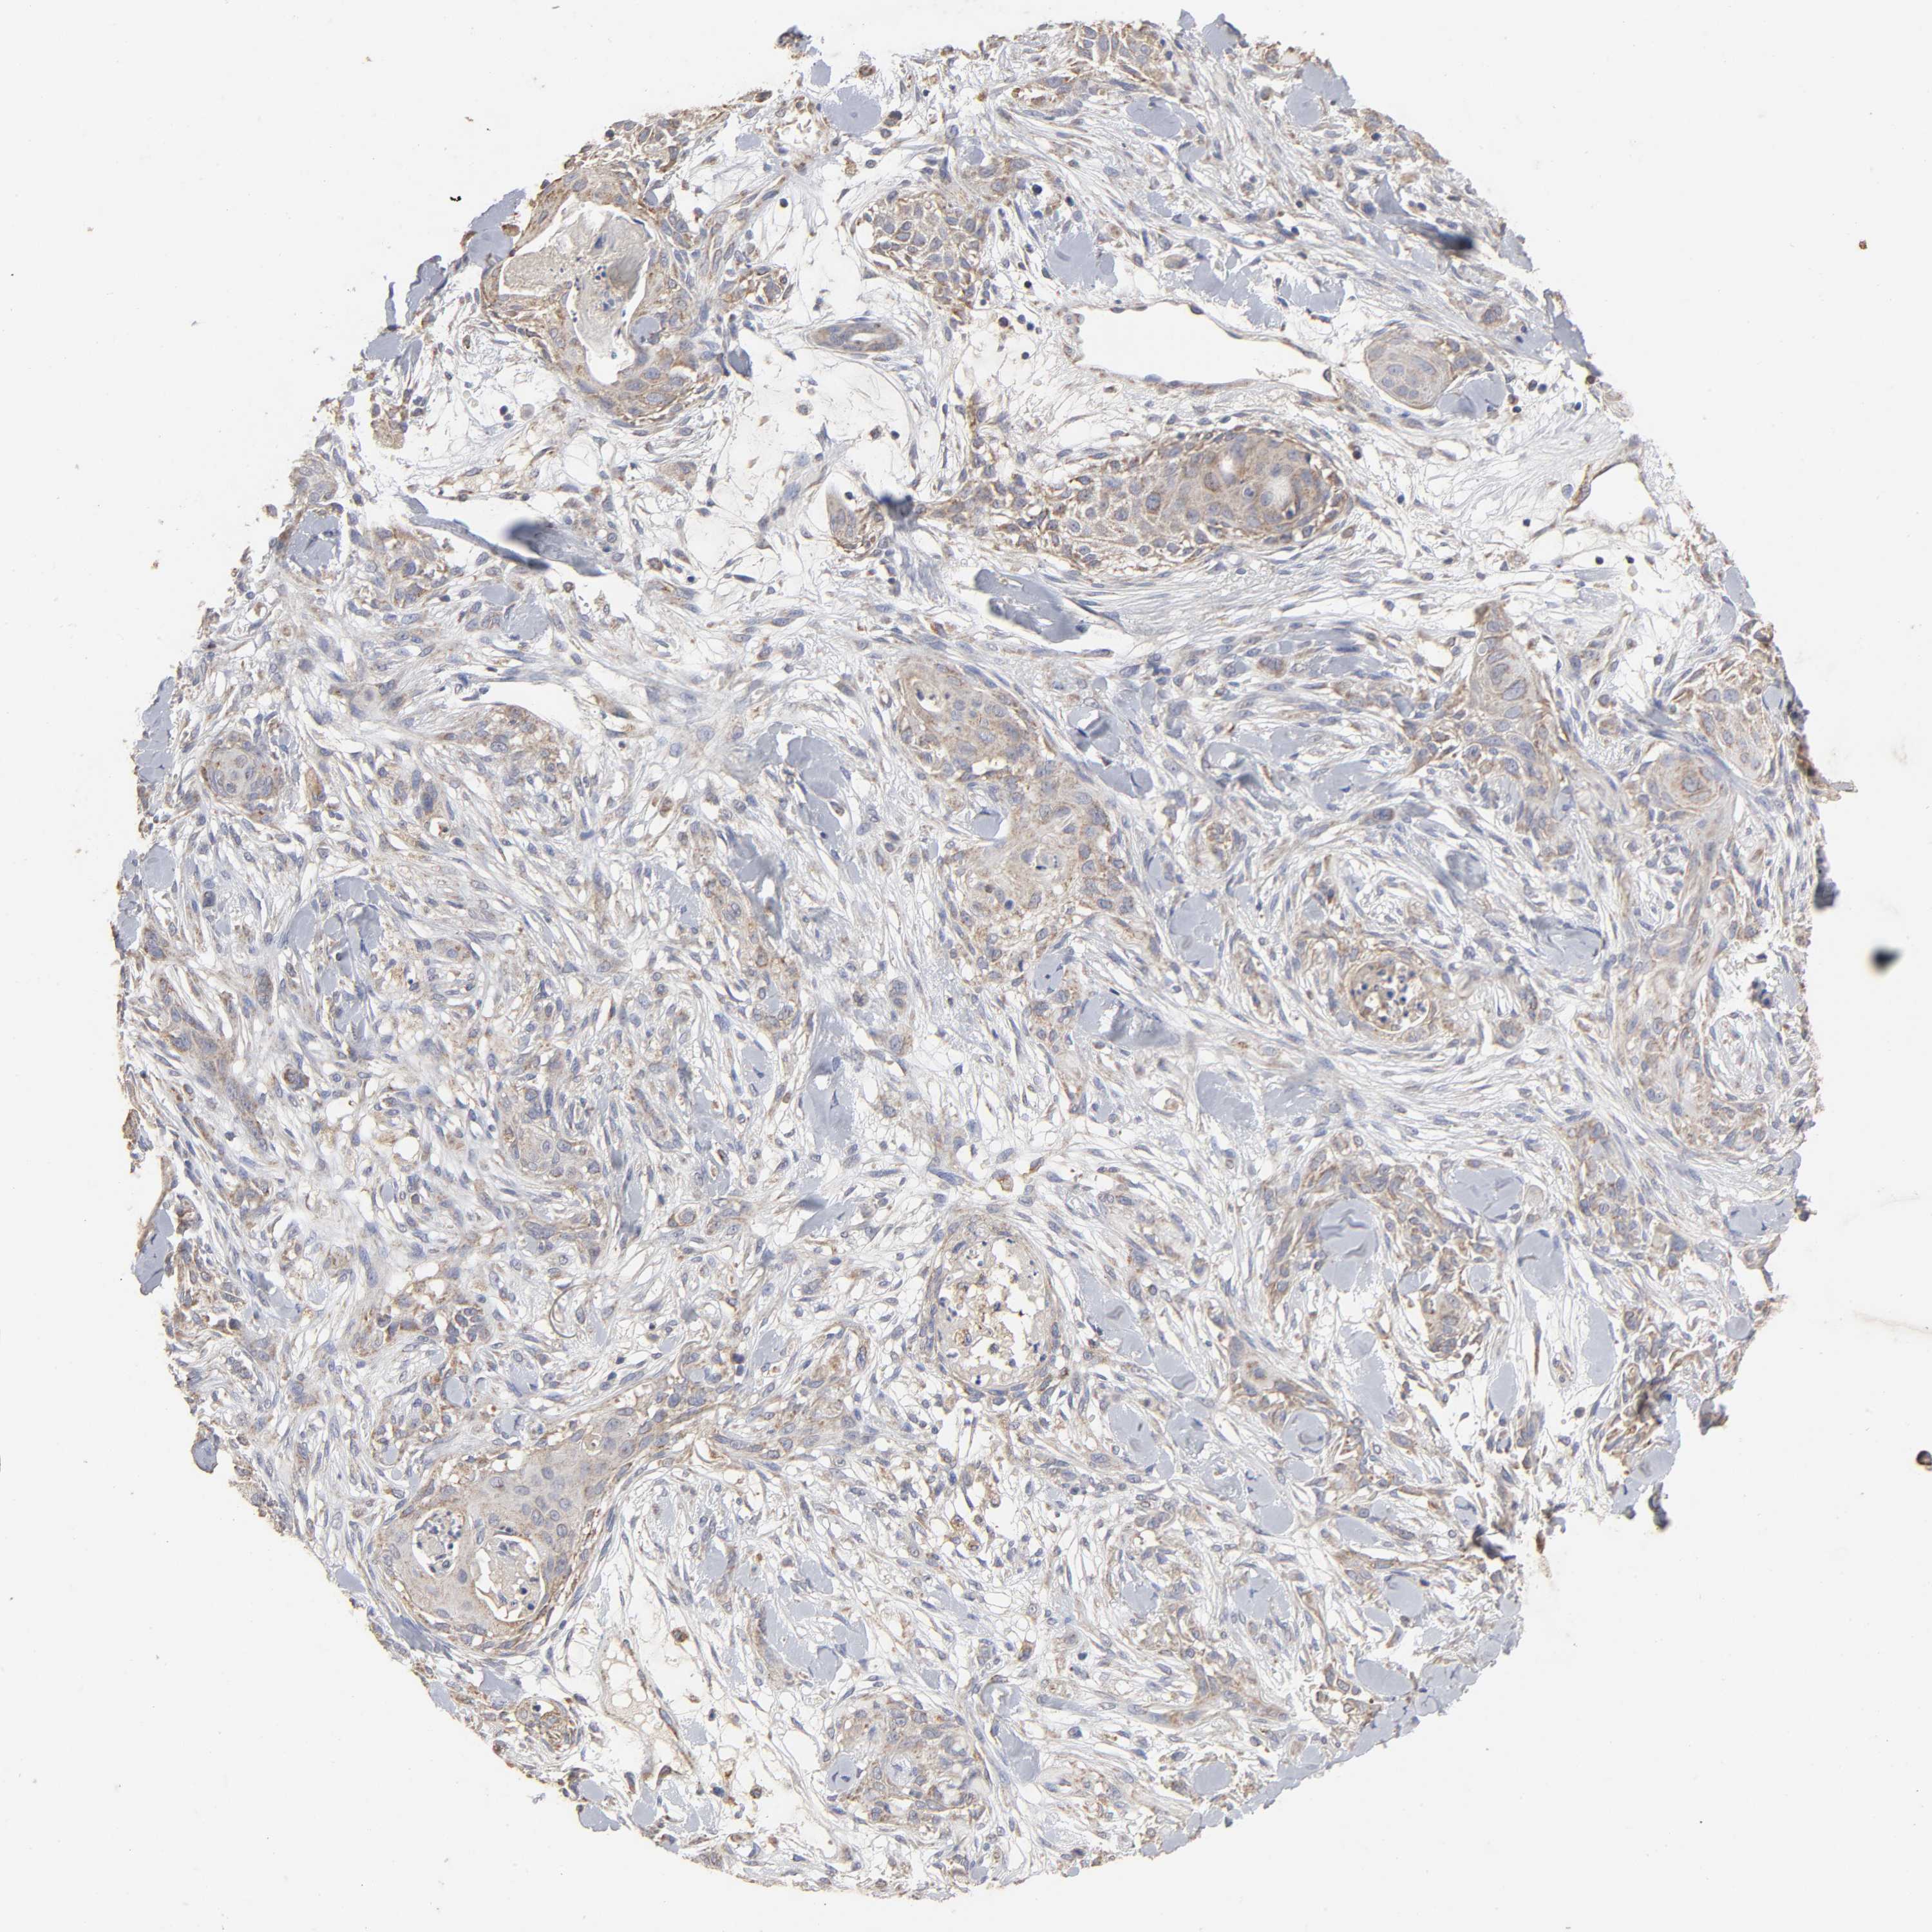

SKIN CANCER - Protein expressioni

A mouse-over function shows sample information and annotation data. Click on an image to view it in a full screen mode. Samples can be filtered based on level of antibody staining by selecting one or several of the following categories: high, medium, low and not detected. The assay and annotation is described here.

Antibody stainingi

Antibody staining in the annotated cell types in the current human tissue is reported as not detected, low, medium, or high, based on conventional immunohistochemistry profiling in selected tissues. This score is based on the combination of the staining intensity and fraction of stained cells.

Each image is clickable and will lead to virtual microscopy that enables deeper exploration of all samples and also displays staining intensity scores, fraction scores and subcellular localization as well as patient and tissue information for each sample.

Antibody CAB005126

Staining

High

Medium

Low

Not detected

Intensity

Strong

Moderate

Weak

Negative

Quantity

>75%

75%-25%

<25%

None

Location

Nuclear

Cytoplasmic/membranous

Cytoplasmic/membranous,nuclear

Basal cell carcinoma

Squamous cell carcinoma, NOS

Squamous cell carcinoma, metastatic, NOS